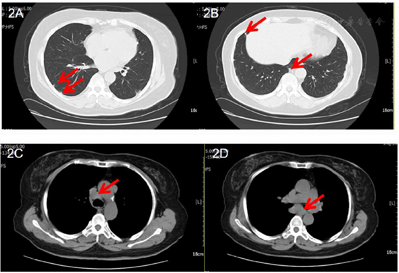

专科检查:面部及全身未见皮疹,浅表淋巴结未扪及肿大。心肺腹查体未见异常,各关节无压痛及肿胀,双下肢不肿。辅助检查:血、尿、便常规、肝功能、肾功能未见明显异常;红细胞沉降率(ESR)12 mm/h,C-反应蛋白1.67 mg/L;肿瘤标记物、干扰素刺激淋巴细胞增殖试验(T-spot)未见明显异常;抗核抗体(ANA)阳性(1:320),抗ENA抗体谱、ANCA阴性;免疫球蛋白(immunoglobin,Ig)G 10.90g/L,IgA 2.54g/L,IgM 1.58g/L,补体C3 0.84 g/L,补体C4 0.19 g/L;胸部CT:双肺可见多个结节(图2A、B);纵隔内多发增大淋巴结,部分融合,较大者位于气管隆突下(图2C、D)。眼部检查:双眼角膜色素性沉着(keratic precipitate,KP)(++)。